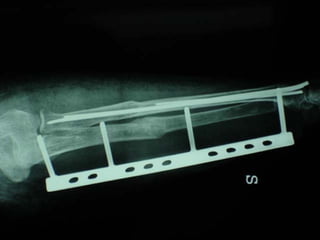

Dal Gennaio 2000 al Febbraio 2006 abbiamo trattato 167 fratture chiuse  con placca percutanea  in 164 pazienti :  27 lesioni diafisarie di gamba, 12 piloni tibiali ,  11 fratture prossimali di tibia, 36 fratture sovracondiloidee di femore, 17 fratture diafisarie di femore, 43 fratture metaepifisarie prossimali di omero, 21 diafisarie d’omero.  156 guarigioni 8 fallimenti

I buoni risultati ottenuti dipendono da 5 punti fondamentali:   una accurata riduzione percutanea della frattura  precise vie di accesso  l’utilizzo della placca che consenta il più lungo braccio di leva possibile il pretensionamento della placca  una sintesi con un ridotto numero di viti

Placche lunghe e pretensionate

Placche lunghe e pretensionate Sintesi con un ridotto numero di viti